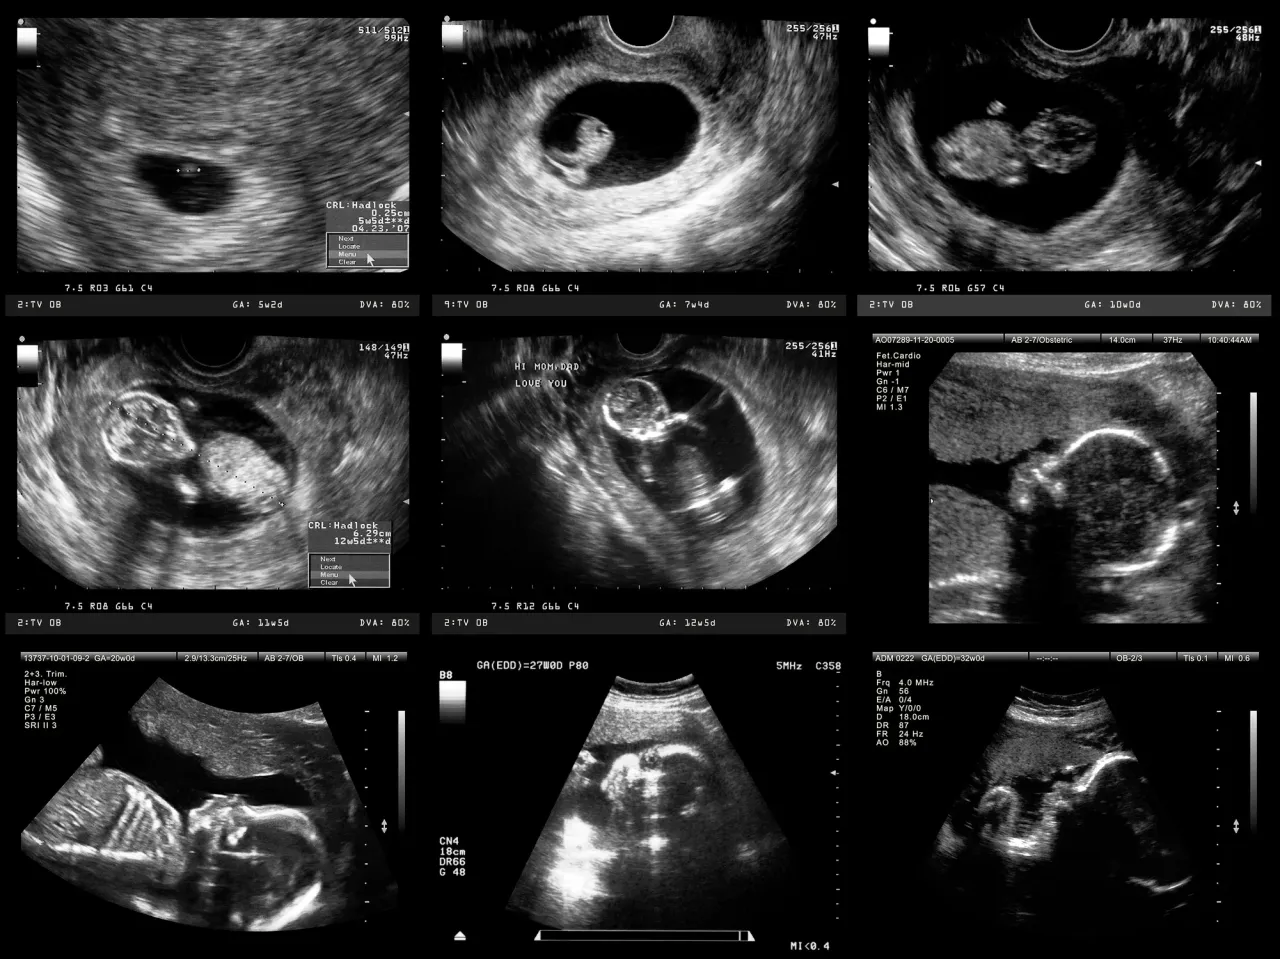

Pierwszy trymestr ciąży to czas, w którym rozpoczyna się kluczowy etap diagnostyki prenatalnej. USG genetyczne, nazywane również USG I trymestru, wykonuje się między 11. a 14. tygodniem ciąży, a idealny moment na nie to okres między 12. a 13. tygodniem (dokładnie między 11+1 a 14+1 tygodniem). Podczas tego badania lekarz ocenia szereg istotnych parametrów płodu. Należą do nich między innymi:

USG połówkowe (18-22 tydzień): Na co lekarz zwróci szczególną uwagę?

Drugi trymestr ciąży to moment, w którym przeprowadzane jest jedno z najważniejszych badań ultrasonograficznych USG połówkowe, nazywane również USG II trymestru. Zaleca się jego wykonanie między 18. a 22. tygodniem ciąży (niektóre źródła podają możliwość wykonania do 23. tygodnia). Badanie to pozwala na bardzo szczegółową ocenę anatomii płodu. Lekarz dokładnie analizuje:

USG III trymestru (28-32 tydzień): Jak rośnie Twoje dziecko?

W trzecim trymestrze ciąży, orientacyjnie między 28. a 32. tygodniem, wykonuje się ostatnie rutynowe badanie ultrasonograficzne USG III trymestru. Jego głównym celem jest ocena dobrostanu płodu i jego rozwoju w końcowym etapie ciąży. Lekarz skupia się na kilku kluczowych aspektach: